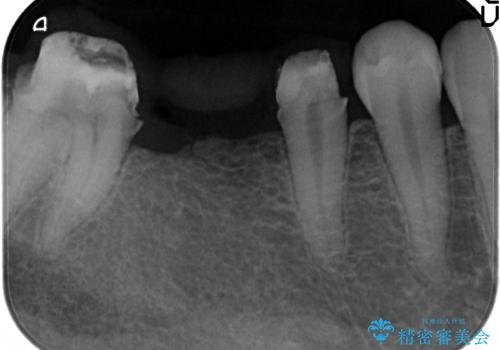

- 上下1本づつの歯を失い、噛めないことの改善を求めて来院されました。

保存可能な歯の虫歯・根管治療を行い、喪失した部分はインプラントを埋入、オールセラミックジルコニアクラウンを製作し審美的に仕上げていきます。

今回下顎の欠損部位はブリッジも検討されましたが、並行性の観点から最後方臼歯の神経を取るリスクを抑えるためインプラント治療を選択しました。